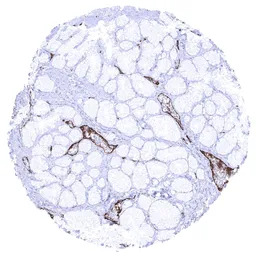

IHC-P analysis of human duodenum Brunner gland tissue section using GTX04412 VWF antibody [MSVA-521R] HistoMAX.

In the Brunner gland endothelial, VWF immunostaining is strongest in venules.